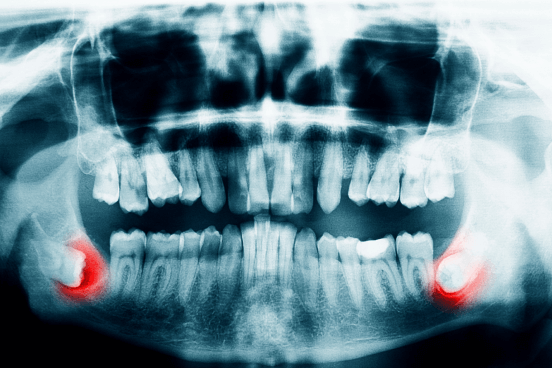

• 親知らずの

炎症による痛み

顎が腫れてズキズキ痛む、奥歯の近くから変な臭いがして、膿が出るなどの症状が出る場合は、親知らずの周りの歯茎が菌に感染して炎症を起こしていることが疑われます。

• 歯科口腔外科

歯科口腔外科

親知らずの抜歯から顎関節症の治療等、口腔(口の中)や顎(あご)、顔面に現れる病気の治療を行います。大きな手術が必要となった場合や、より専門的な治療が必要であると判断した場合は、当院の提携病院を紹介させていただきます。